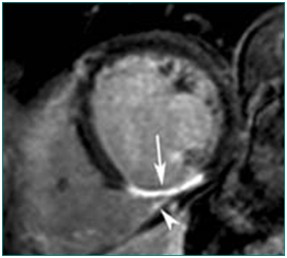

心肌灌注(病例-心肌梗死)